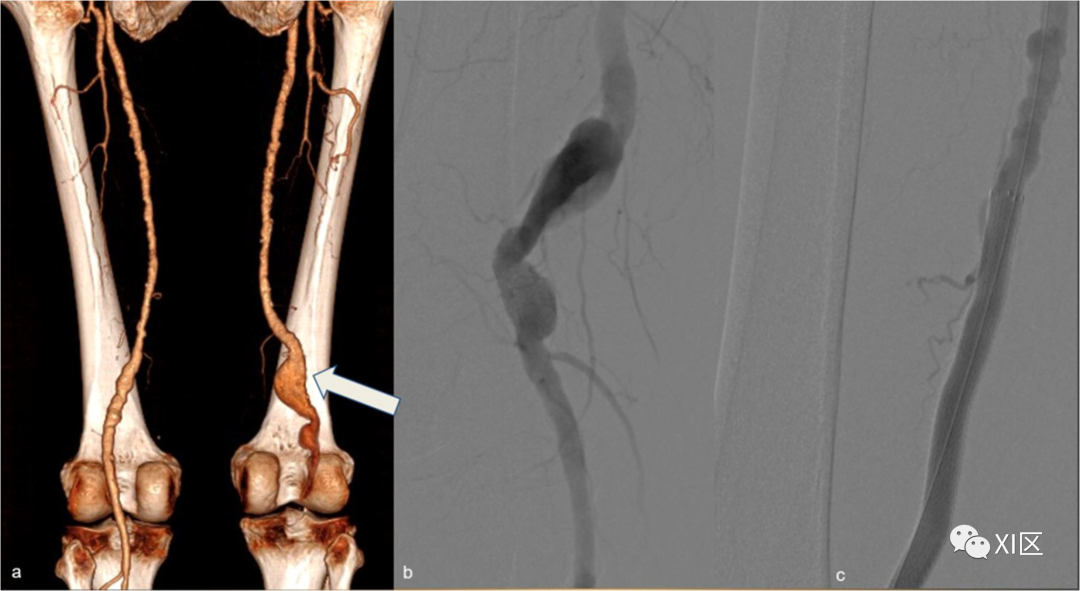

假性动脉瘤(图12)是由动脉壁层的不完全破裂引起的,在CTA中,血管附近有圆形的、清晰的造影剂积聚,可以很容易地与活动性出血区分开来,因为它们是不规则的腔内造影剂池,而且,与持续出血不同的是,假性动脉瘤中的造影剂积聚在延迟期采集时不会发生大小变化。

图12 假性动脉瘤。37岁吸毒男性患者,在穿刺注射药物后出现搏动性腹股沟肿块,进行CTA检查。右侧腹股沟的轴位平扫图像显示腹股沟血肿(白色箭头)。b 右腹股沟动脉期图像,显示清晰的血管外对比剂积聚(黑色箭头)。在MIP重建(c)中,来自右股浅动脉的成分来源非常明显,并确认了假性动脉瘤的诊断。